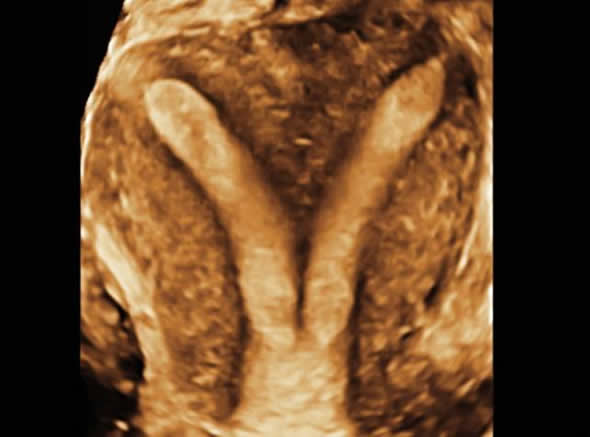

الكشف بجهاز سونار ثلاثى الأبعاد

لماذا الكشف بالجيل الأخير من أجهزة السونار ثلاثية ورباعية الأبعاد في حالات تأخر الحمل؟

تتميز الأجهزة التي بها خاصية ثلاثي الأبعاد بدقة متناهية في الدقة والوضوح.

أن السونار ثلاثي الأبعاد يعمل مسح كامل لجميع أجزاء الرحم والمبيضين ولهذا يمكن دراسة كل جزء ولو صغير بدقة متناهية وهو ما يعني تشخيص دقيق أفضل وبالتالي نتيجة أفضل

أن السونار ثلاثي الأبعاد يعمل مسح كامل لجميع أجزاء الرحم والمبيضين ولهذا يمكن دراسة كل جزء ولو صغير بدقة متناهية وهو ما يعني تشخيص دقيق أفضل وبالتالي نتيجة أفضل اقرأ المزيد